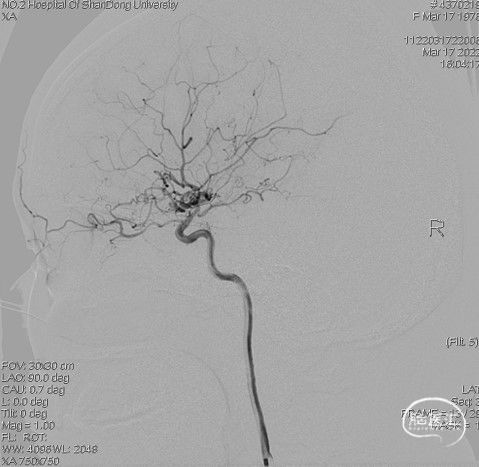

病人乙的影像资料:

造影:右侧颈内动脉末段变细,右侧大脑中动脉M1段分叉前重度狭窄,豆纹动脉增多,右侧大脑前动脉向大脑中动脉分布区代偿供血:

右侧颈内动脉正位:

右侧颈内动脉侧位:

三维重建显示右侧大脑中动脉分叉前部重度狭窄,狭窄段直径0.4mm,狭窄程度约84%: